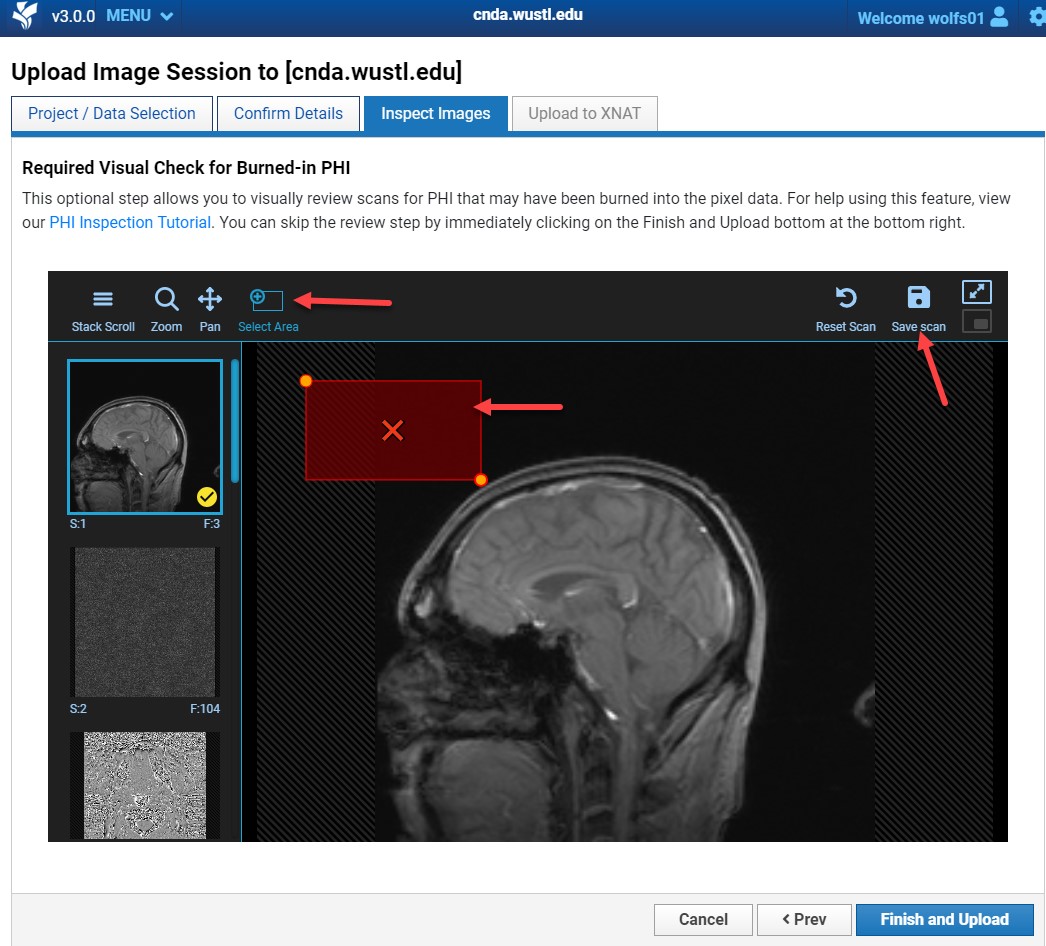

Removing Burned-In PHI

If PHI is found:

- Click the Select Area tool.

- Draw a box around the PHI.

- Apply to the series.

- Click Save Scan.

- Repeat for all affected series.

- Click Finish and Upload.